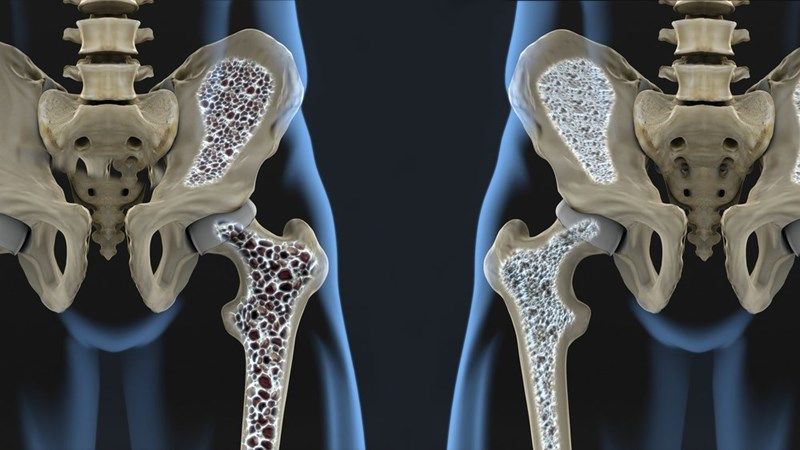

Durante nuestros años de juventud jamás nos preocupamos por cómo será nuestra salud a medida que envejecemos. Debido a que más mujeres que mueren de enfermedades cardíacas y ahora a casi la mitad de la población femenina se les diagnostica osteoporosis (pérdida de densidad ósea) cuando llegan a los 60 años, ya es hora de tomar cartas en el asunto.

Más preocupante aún es que 1 de cada 5 mujeres sufrirá una caída cuando tengan 60 años y podría romperse la cadera. Debido a la osteoporosis, podría significar que los huesos no sanarán y nunca podría caminar nuevamente. Sin embargo, existen mujeres de tan solo 20 años que arrojan pruebas con baja densidad ósea. Pero hay una solución increíblemente simple y también afecta el riesgo de enfermedad cardíaca.

Quizás le parezca terrible y pueda pensar que no tiene relación alguna, pero aquí hay algunos hechos interesantes sobre por qué hacerse vegetariana podría reducir drásticamente el riesgo de padecer esta enfermedad: La razón es que el consumo excesivo de carne está causando la pérdida de densidad ósea.

Existen estudios que revelan que la carga de ácido renal de las carnes, el queso y otros productos animales podría estar contribuyendo a la pérdida ósea. El estudio dice: “Una de las controversias más debatidas en la actualidad sobre la nutrición clínica es si una dieta con una mayor cantidad de proteína tiene un efecto positivo o negativo sobre la fortaleza ósea y la densidad mineral ósea (DMO)”

Las personas que no consumen proteínas animales indican que los vegetarianos tienden a tener huesos más fuertes que las personas que comen más carne y los ensayos clínicos que muestran una mayor pérdida de calcio en la orina cuando aumenta la ingesta de carne o proteína.

Cualquier actividad que cause inflamación crónica de bajo grado también contribuye a la osteoporosis. Aunque comer carne no es el único responsable, un estilo de vida sedentario, azúcar refinada, grasas refinadas, etc. también aumentan la acidez, el consumo de carne sí causa inflamación.